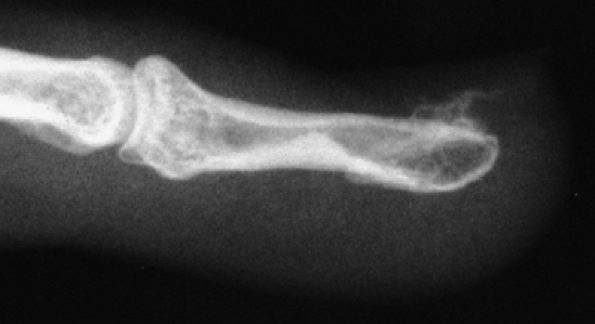

tendon. A sudden hyperextension during active flexion is responsible for this type of avulsion, most often seen in young athletes.75 The ring finger is involved in 80% of cases. This injury is often neglected initially as there is no typical deformity and swelling. Pain may mask a loss of active flexion of the DIP joint. Jersey finger is classified according to the degree of tendon retraction and the presence or absence of a bony fragment (Fig. 11.46):76,77

-

Type I: Retraction of the tendon into the palm

Type II: Retraction at the PIP joint. A small bone fleck may avulse and is visible at the PIP level.

Type III: Large bony fragment incarcerated in the A4 pulley

Type IV: A type III injury with an associated avulsion of the flexor tendon from the bone fragment